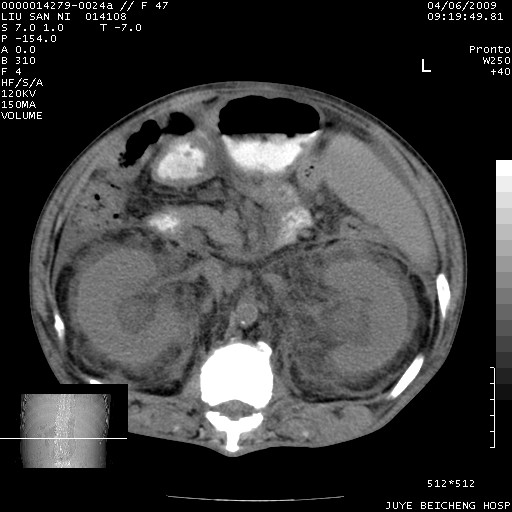

以下是引用前行在2009-4-7 10:31:00的发言:[br]肝脾肿大;双肾增大,双肾盂少量积水可能,肾膜膜增厚,肾周间隙增宽,并见桥间隔,提示结缔组系统疾病、系统性红瘢狼疮肾可能性大。继发右侧胸腔、心包、腹腔积液。

以下是引用深泽交通医院在2009-4-7 11:21:00的发言:[br]双侧肾周密度增高,见条索影,右肾实质见点片状低密度区,考虑弥漫肾炎【自身免疫性?】;;肾性水肿征